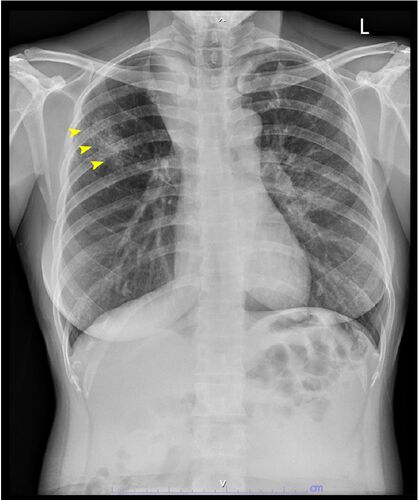

症例107:39歳女性、急激に進行する呼吸不全(J Am Coll Emerg Physicians Open. 2020 Dec 15;2(1):e12333.)

病歴/身体所見 ・39歳女性 ・2日間持続する呼吸困難のためER受診 ・受診時呼吸回数30回/分であり、whezing+stridorが聴取されていた ◦呼吸補助筋使用はなし ・気管支拡張薬が迅速に投与されたが症状は改善しなかった その後の経過 ・受診から2時間後、呼吸困…